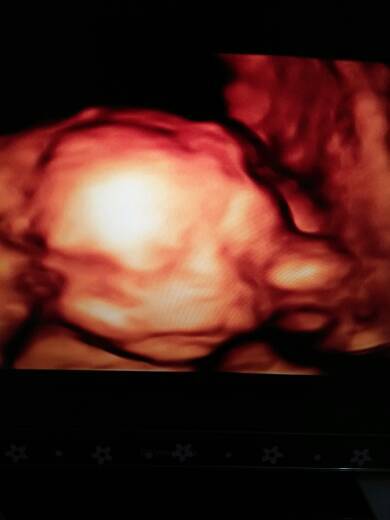

怀孕22周做的四维,B超单医生说正常,但是照片有一张像兔唇,其他几张还好

一般如果有兔唇的话医生也会告知的。

看不清楚你发的图片啊

不一定是异常的,不放心可以2周后复查,明确看起来不是很明显的是。